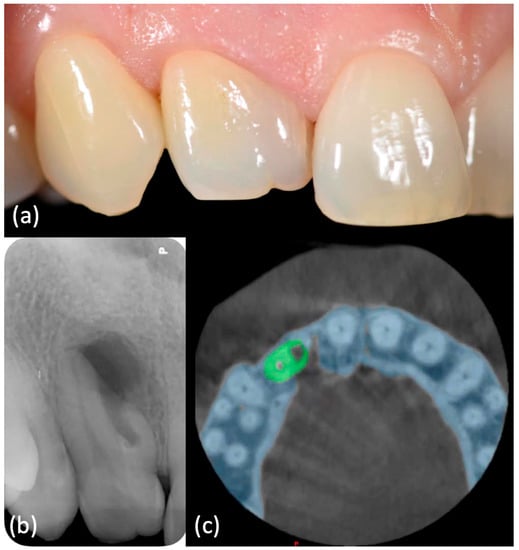

One week later, no discomfort has been reported and primary tissue healing had been achieved, allowing sutures removal (Figure 5a). Clinical (Figure 5b) and radiographic follow-up (Figure 5c,d) showed a positive outcome, with soft tissue and bone healing progression.

Tissue healing after (a) one week and (b) six months and (c) six-months and (d) twelve-months radiographic follow-up.

History and physical examination: A 16-year-old otherwise healthy female was seen in emergency because of pain in her right maxillary region. An extraoral examination did not reveal swelling or other abnormalities. An intraoral examination showed immediately the presence of a lump on the buccal aspect of the tooth 26, which appeared not to be completely erupted and with a typical aspect of dilacerated root morphology on 2D radiographic imaging. A carious lesion was present on the same tooth and element 27 was not erupted (Figure 6a–Movie 6).

(a) Intraoral examination showed a lump on buccal side of element 2.6, which appeared not to be completely erupted and with a carious lesion. Element 2.7 was clinically absent. (b) Periapical X-ray showed dilacerated roots of element 2.6, with a periapical lesion on the mesial-buccal one. Element 2.7 was not erupted, but present. (c) CBCT confirmed these findings and highlighted a periapical lesion also on the other roots.

Imaging examination and diagnosis: A pre-operative periapical image (Figure 6b) was carried out by long-cone paralleling technique (CS 2200, Carestream Dental, Rochester, NY, USA). It confirmed the presence of dilacerated mesio- and disto-buccal roots and the diagnosis of chronic periapical periodontitis. The tooth 27 was not erupted because of aberrant root morphology of the mesial element.

This radiography had an important role in the preliminary assessment of the irregular morphology of the root canal system, but it provided only a 2D-representation of the complex anatomy. Therefore, a small-FOV CBCT (Figure 6c–Movie 7) was indicated based on the current ESE guidelines. It provided a 3D image of the dilacerated tooth and its surrounding tissues and helped to determine the exact position and angulation of the dilaceration abnormality, which was found to also affect the palatal root. Apical radiolucencies were detected within the woven bone surrounding the apices of all roots. These diagnostic findings could be obtained only with CBCT imaging. An orthograde primary root canal treatment was recommended to the patient.